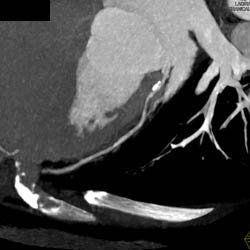

Plaque in LAD